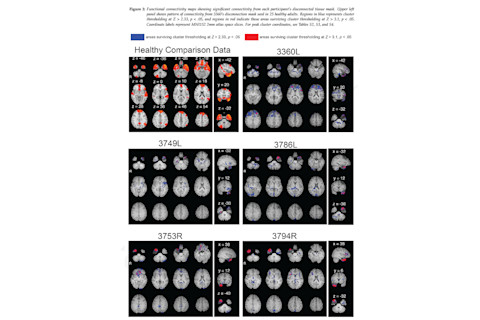

A new article posted on preprint site bioRxiv has generated a lot of interest among neuroscientists on Twitter. The article reports the existence of 'functional connectivity' between surgically disconnected distant brain regions using fMRI, something that in theory shouldn't be possible. This is big news, if true, because it suggests that fMRI functional connectivity isn't entirely a reflection of actual signalling between brain areas. Rather, something else must be able to produce connectivity - most likely it has to do with the constriction of blood vessels in the brain. Whatever the source of the non-neuronal connectivity is, it raises the worrying possibility that it might be contaminating fMRI studies. The research comes from a University of Iowa team, with the first author being David E. Warren. Warren et al. studied 5 patients who'd had surgery to disconnect one of their temporal poles, for epilepsy treatment. Here's the resting state fMRI connectivity of the disconnected temporal pole (seed-voxel) within each subject, compared to the pattern of connectivity in healthy subjects with the same temporal pole seed.

In a nutshell, the results shows that in each of the five subjects, there were areas which were significantly "connected" to the disconnected temporal pole. Different brain areas were involved in different subjects, and the connectivity was relatively weak, with most blobs only appearing at the Z>2.33 cluster defining threshold and not the more robust Z>3.1 threshold. Warren et al. conclude that their results cast doubt on the nature of fMRI connectivity: